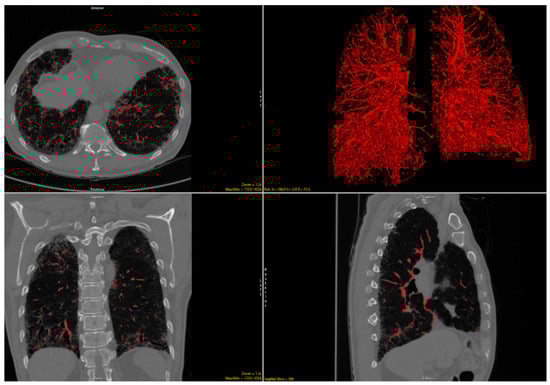

2.2. Imaging Analysis